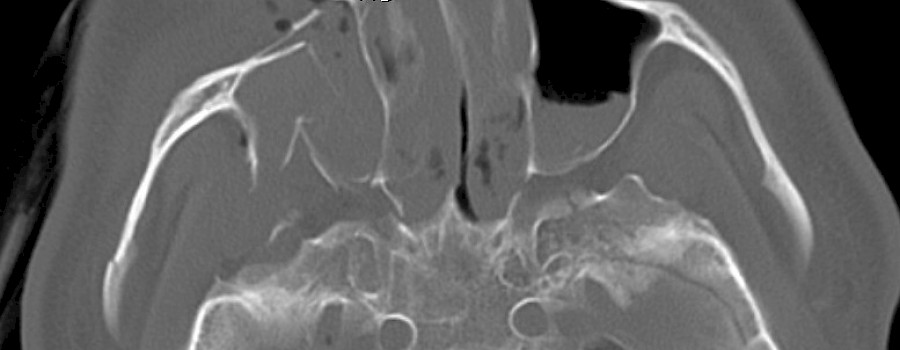

Ein Autofahrer war auf der BAB unterwegs, bis er von der Fahrbahn abkam. Er wurde mit dem RTW in das nächste Krankenhaus gebracht, wo er dann als Polytrauma-Patient im Schockraum behandelt wurde.